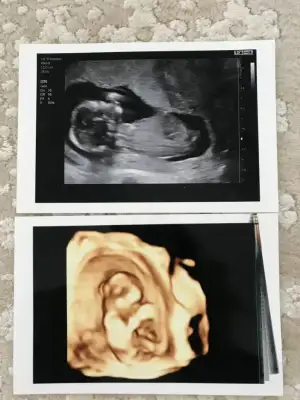

Merhaba, yorumlayabilir misiniz :anneadayı:

Eklentiler

• 20190820_130938.webp

20190820_130938.webp

17,4 KB · Görüntüleme: 87